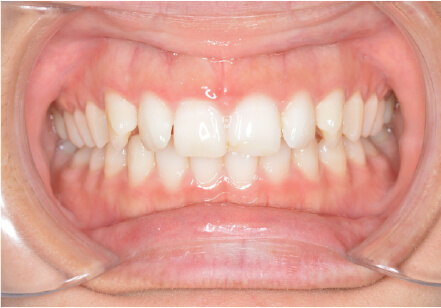

9歳

/

男性

相談内容

下の歯が重なっている。

カウンセリング・診断結果

myoからの移行

治療内容・方法

全額アライナー矯正

術後の経過・現在の様子

上下3〜3fix使用

治療のリスク

痛み・歯根吸収・歯肉退縮・虫歯・後戻り

費用・治療期間

880,000円、1年2ヶ月